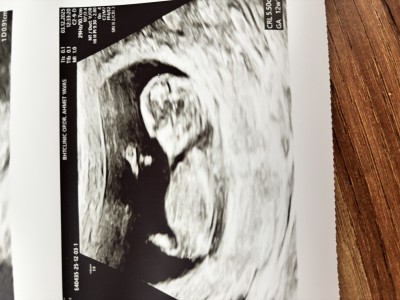

Cinsiyet hakkında haydi yorumlayın

Gebelik haftası 12+1

En uçta bir çıkıntı var kimisi erkek diyor ben de kıza benzettim

Nub teorisine göre kıza benziyor